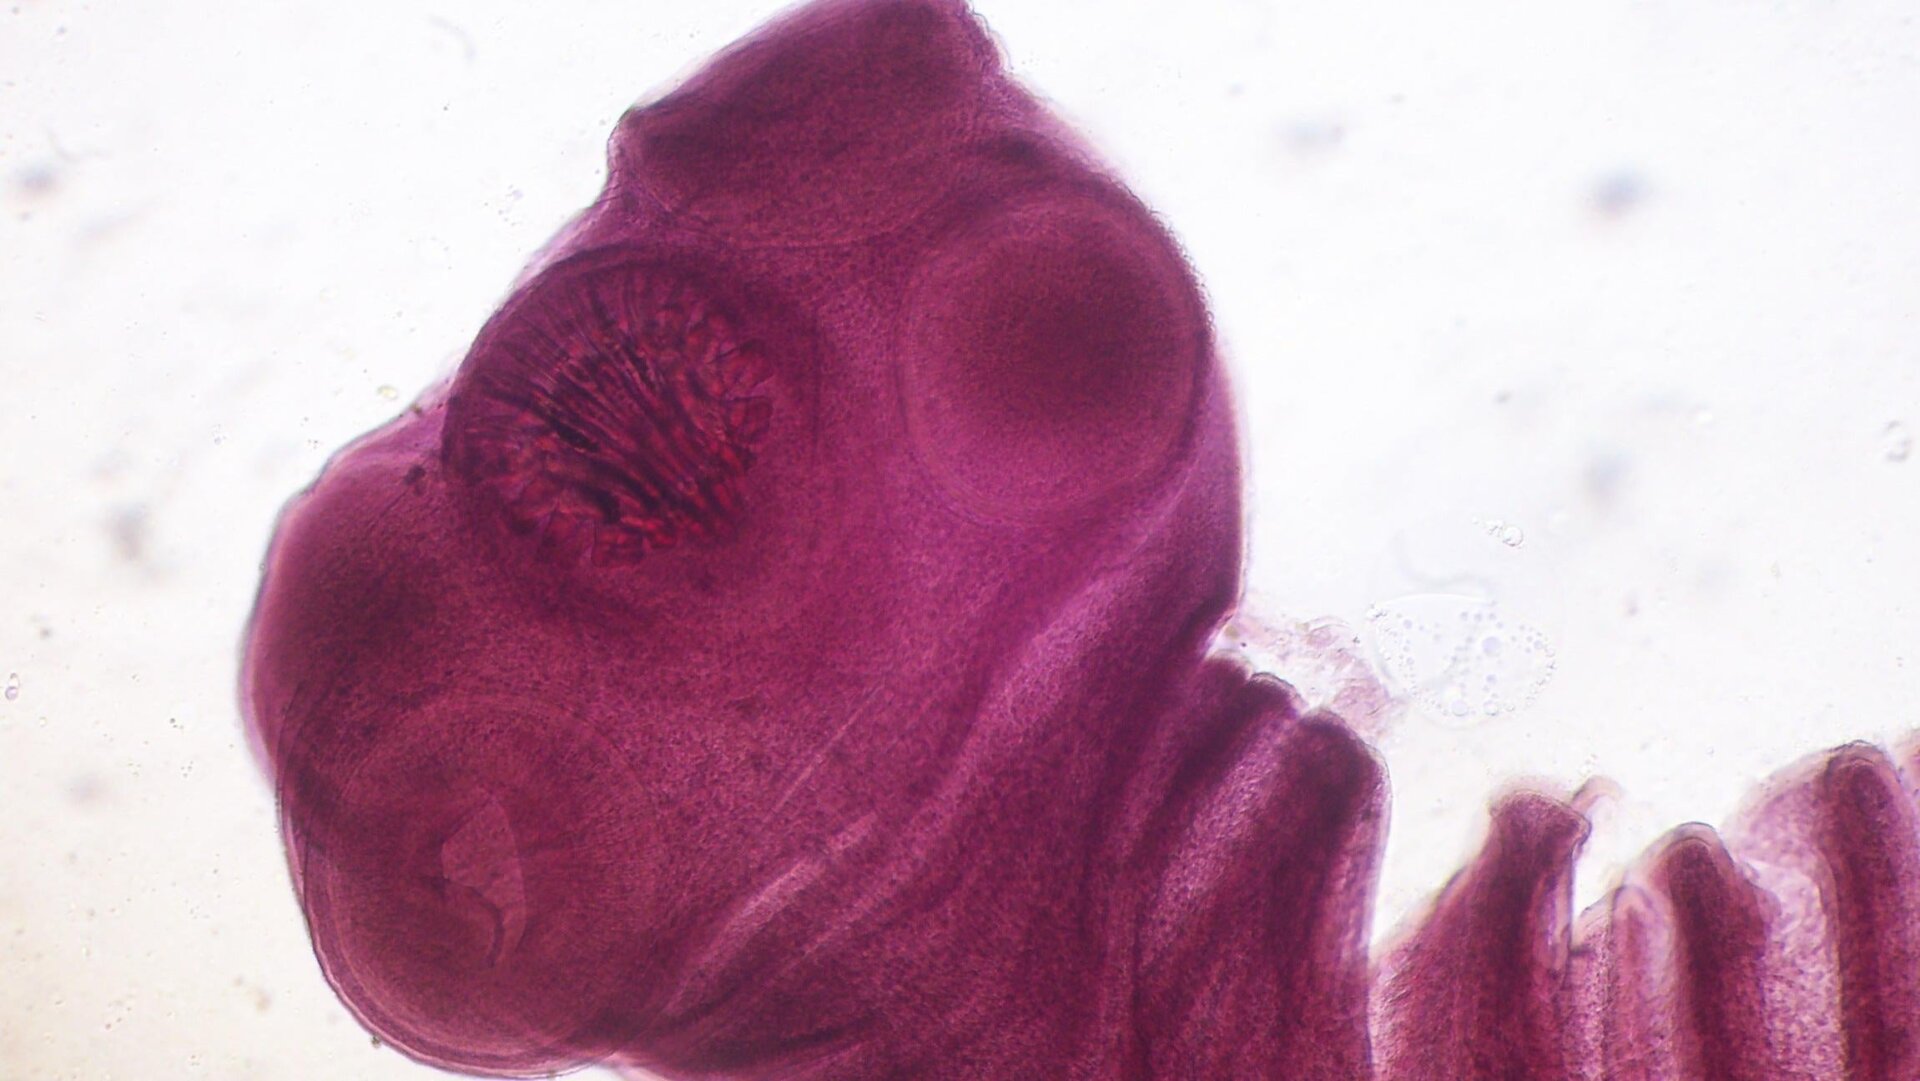

The man had no history of underlying health problems, and, according to his family, he had been completely fine the day before. Once doctors were able to run CT and MRI scans of his brain, though, the likely culprit of his illness was found: calcified and long-since-dead larval tapeworm cysts. Doctors then concluded that he had a relatively rare form of infestation from the pork tapeworm (Taenia solium), known as neurocysticercosis.

But if another human or even the same infected human then ingests these eggs, the new generation of worms reaches a dead end and can only mature into their cyst form of life. Unfortunately, the nightmare doesn’t end there, because these cysts can still wreak havoc wherever they end up. When they get stuck in the brain, they can cause pressure and trigger inflammation that leads to all sorts of neurological symptoms, including seizures and even death. But it can take years or decades following infestation for symptoms to show up, often only after the worm cysts die (adult tapeworms can live up to 30 years in a host; cysts have a shorter lifespan of around five years). Sometimes, the cysts and the trouble they cause can be confused for a brain tumor.